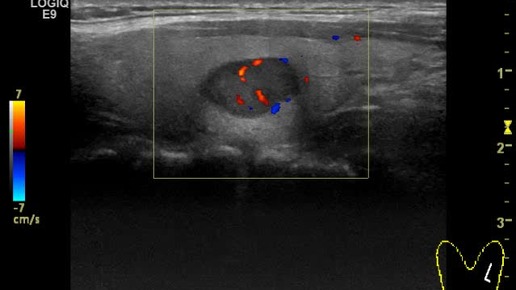

Видео к статье "Общие принципы ультразвукового анализа узлов щитовидной железы" Ссылка на статью https://dzen.ru/a/ZtlFLWAI93Gg_c_j